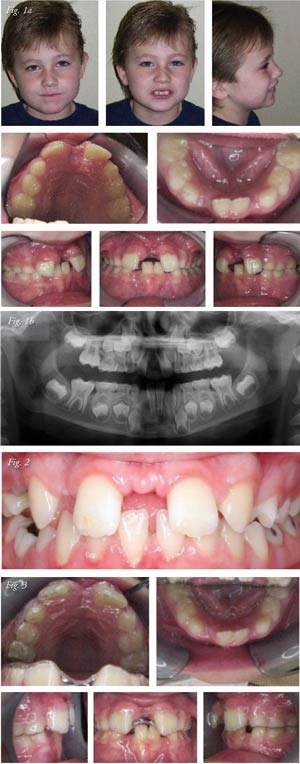

On July 10, 2008, I examined a six-year-old autistic

patient that was referred by his pediatric dentist for evaluation of

a large diastema between the upper central incisors. The unsightly

space between the centrals was exaggerated by a previous medical

intervention during a tonsillectomy. The ENT physician informed

the parents that during the tonsillectomy he assisted the dental

issue of the diastema by doing a "frenectomy." Figures 1a and 1b

show the condition that existed at the initial examination.

Notice that the interdental papilla, which is normally there

(Fig. 2), was now absent after the "frenectomy."